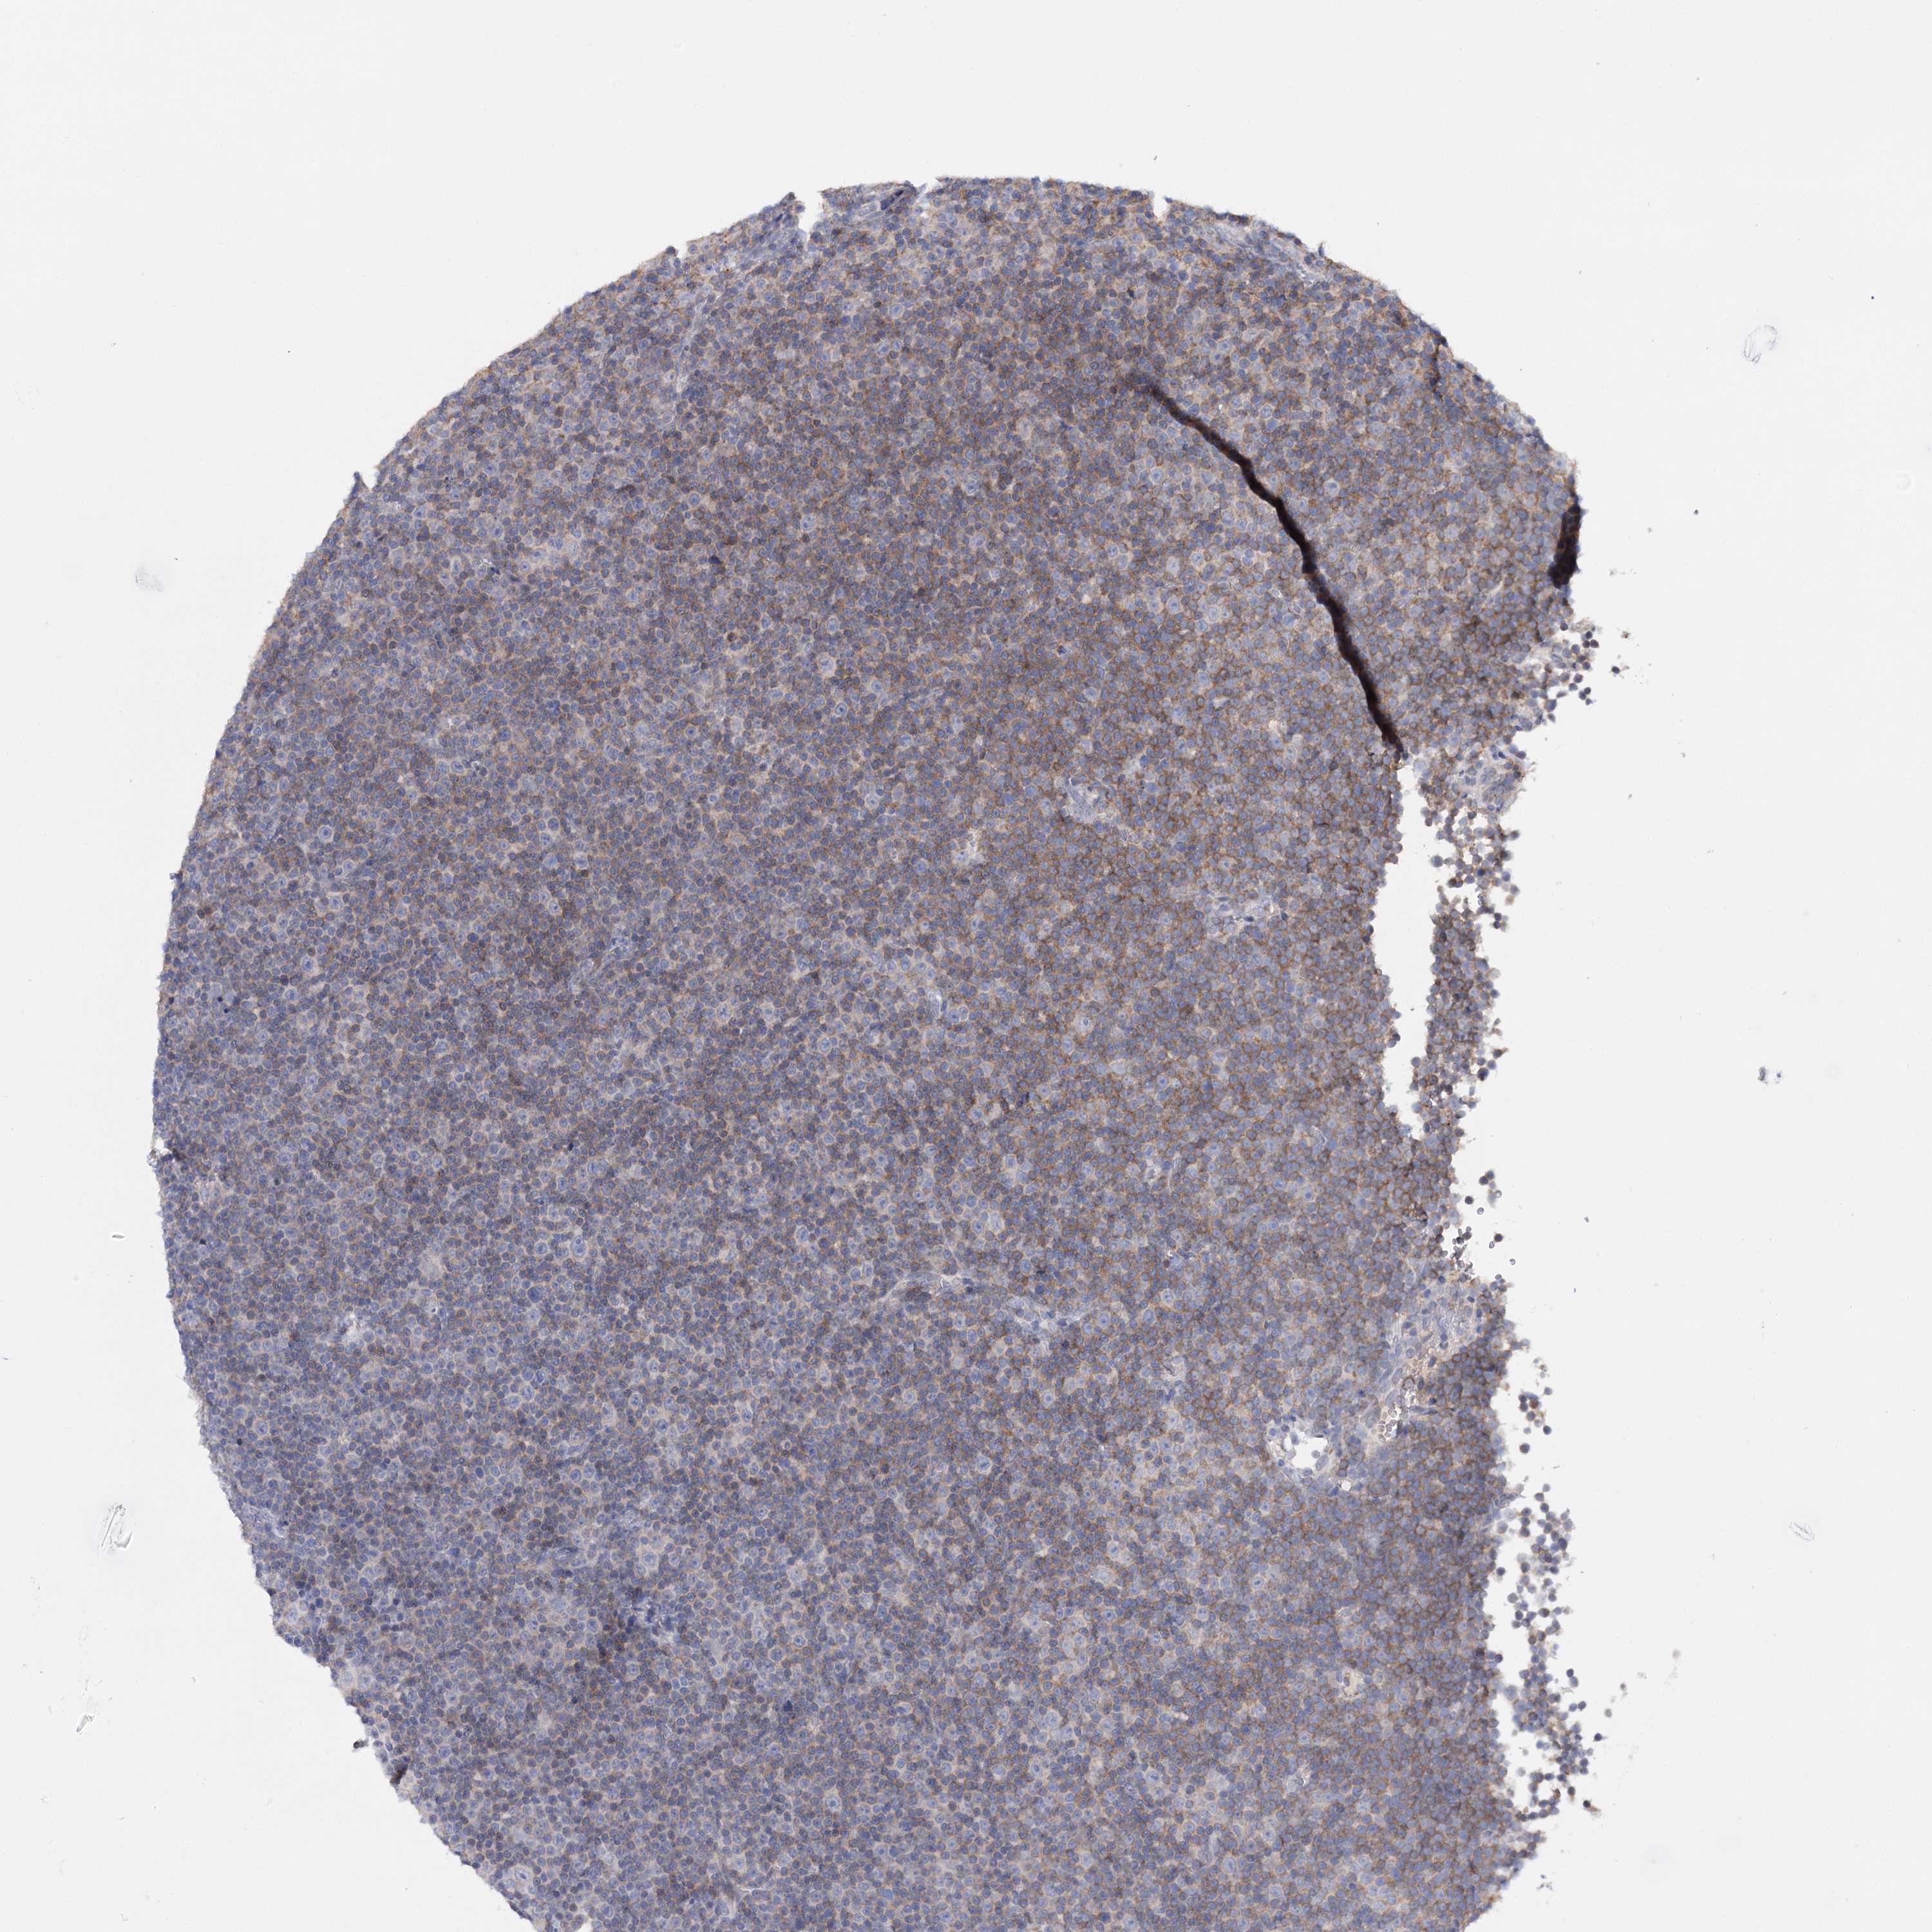

CANCER LYMPHOMA Show tissue menu

LYMPHOMA - Protein expressioni

A mouse-over function shows sample information and annotation data. Click on an image to view it in a full screen mode. Samples can be filtered based on level of antibody staining by selecting one or several of the following categories: high, medium, low and not detected. The assay and annotation is described here.

Antibody stainingi

Antibody staining in the annotated cell types in the current human tissue is reported as not detected, low, medium, or high, based on conventional immunohistochemistry profiling in selected tissues. This score is based on the combination of the staining intensity and fraction of stained cells.

Each image is clickable and will lead to virtual microscopy that enables deeper exploration of all samples and also displays staining intensity scores, fraction scores and subcellular localization as well as patient and tissue information for each sample.

Antibody HPA038034

Hodgkin's disease, NOS

Malignant lymphoma, non-Hodgkin's type, High grade

Malignant lymphoma, non-Hodgkin's type, Low grade